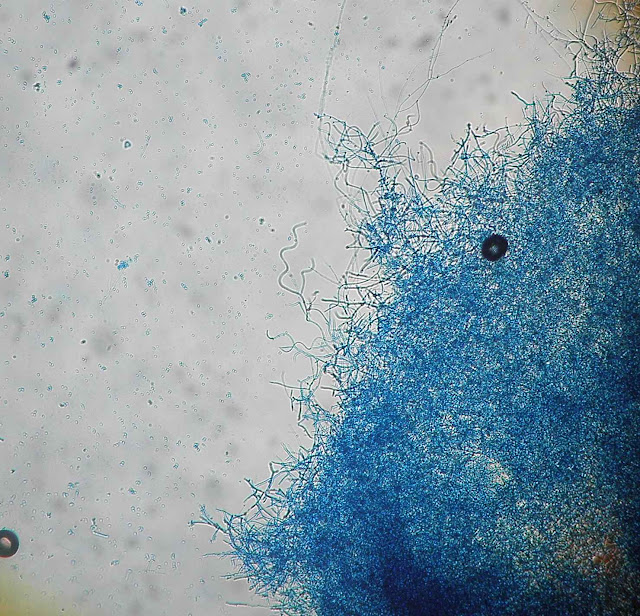

Aspeto microscópico tipico: microconideos abundantes e arredondados dispostos fazendo lembrar cachos de uva.

Hifa e microconideos.

Hifa com microconideos agrupados.

Hifas espiraladas (azul lactofenol).